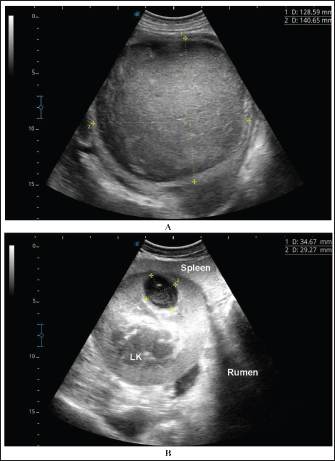

Fig. 9. Ultrasonographic findings in the camels with abscessation of the left kidney (LK). Image A shows a large abscess in camel number 15 with isoechoic contents and a thick capsule. Image B shows a small abscess in the left kidney of camel number 16 with heterogeneous contents.

Ultrasonographic findings in camel number 9 with right kidney abscesses are shown in Figure 7, where the lesion appeared compressing the parenchyma of the right kidney. Its contents are hyperechoic, and its capsule is thick. Figure 8 shows sonographic findings in camel number 11 with abscessation of the right and left kidneys. Abscesses measured 7.6 × 6.9 cm and 9.3 × 8.1 cm with isoechoic contents. A third abscess in the same camel was found within the left kidney. It was relatively large and was isoechoic. Ultrasonographic findings in camels 15 and 16 with abscesses of the left kidney are shown in Figure 9. A large abscess was found in camel number 15 with isoechoic contents and a thick capsule, while a small abscess was imaged in the left kidney of animal number 16 with heterogeneous contents. Figure 10 shows the ultrasonographic findings in camel number 17 with abscessation of the left kidney. A large abscess was found compressing the parenchyma of the left kidney with isoechoic contents. The urinary bladder in the same camel contained echogenic deposits that appeared to be highly echogenic.